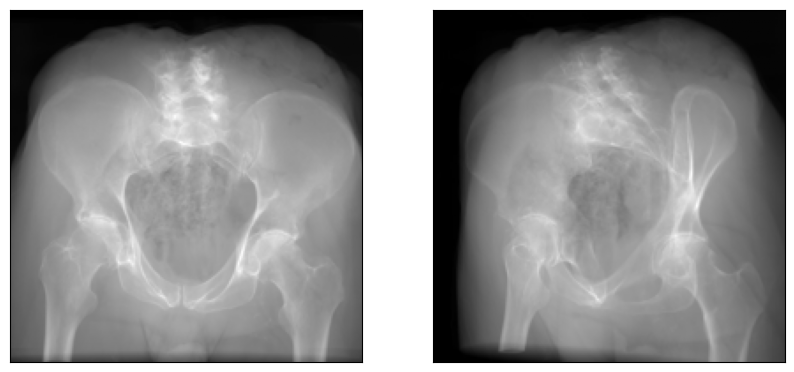

In DiffDRR, we were constrined to rendering X-rays from a single subject with fixed intrinsics. With the functional interface in nanodrr, we can freely exchange the subject and intrinsics, as well as the C-arm pose.

Also, note that the intrinsic matrix can be different for every image being rendered, which is useful for biplane C-arm setups.

torch.Size([2, 8, 200, 200])

As in DiffDRR, if our Subject has a labelmap, the rendered DRRs are multichannel with each channel corresponding to a distinct anatomical structure.

# Sum the intensities across all channels and plot the DRR

plot_drr(img.sum(dim=1, keepdim=True), ticks=False)

plt.show()